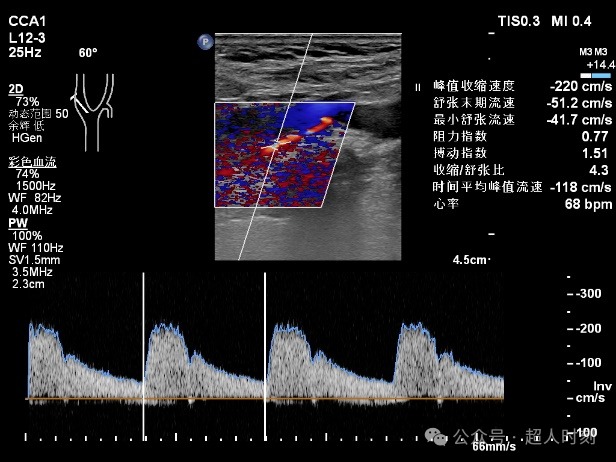

患者,男性,78岁,因“反复头痛头晕‚伴右眼黑朦1+年,肢体麻木偶感上肢无力6+月”入院。颈动脉彩超:右颈内动脉明显狭窄(狭窄率70%-99%),双侧颈总动脉多处狭窄(狭窄率<50%)。TCCD:颅内多支动脉狭窄(见图5)。

图5b 右颈内动脉颈段血流速度增快频谱图